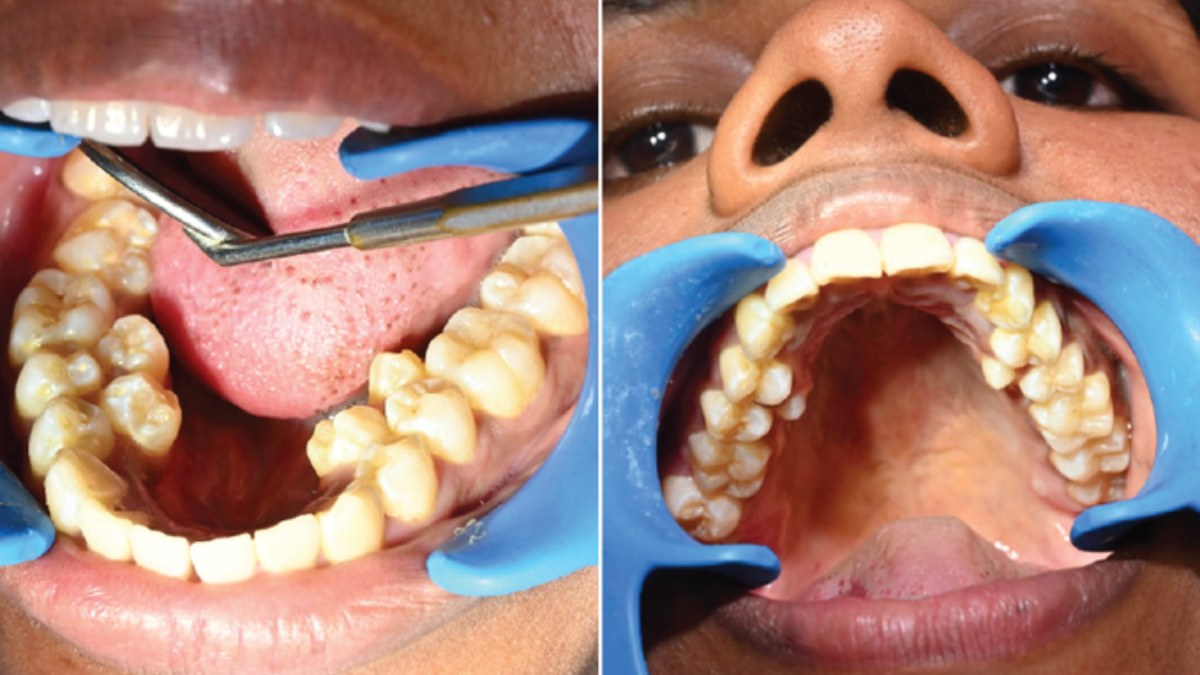

32 కాదు ఏకంగా 38 పళ్లతో గిన్నిస్ రికార్డు సృష్టించిన మహిళ !

పెద్దవారి నోటిలో 32 దంతాలు ఉండటం సహజమే. అయితే ఇక్కడ ఓ మహిళ 38 దంతాలు కలిగి ప్రపంచ రికార్డు సృష్టించింది. తమిళనాడుకు చెందిన ఓ మహిళ సరిగ్గా 38 దంతాలు కలిగి ప్రపంచ రికార్డు సృష్టించింది. వైద్య రికార్డుల ప్రకారం ప్రపంచ జనాభాలో 1% మాత్రమే. 3.8% మందికి మాత్రమే ఈ రకమైన అదనపు దంతాలు ఉన్నాయి. దంతాల సమయంలో అసాధారణ ప్రక్రియలు సంభవిస్తాయి మరియు ఈ రకమైన పరిస్థితి ఏర్పడుతుంది. ఈ రకమైన అసాధారణ దంతాలు సాధారణ దంతాల పక్కనే పెరుగుతాయి.

భారత సంతతికి చెందిన తమిళనాడుకు చెందిన కల్పనా బాలన్ అనే మహిళ ఓ విశిష్ట పనికి గిన్నిస్ వరల్డ్ రికార్డ్ సృష్టించింది. 26 ఏళ్ల కల్పన నోటిలో సరిగ్గా 38 పళ్లు ఉన్నాయి. సాధారణంగా మనిషి నోటిలో 32 దంతాలు ఉంటాయి. అయితే, కల్పనా బాలన్ నోటిలో మొత్తం 38 దంతాలు ఉన్నాయి, 6 అదనపు పళ్ళు ఉన్నాయి, ఇది గిన్నిస్ వరల్డ్ రికార్డ్.

దీనికి సంబంధించిన సమాచారాన్ని గిన్నిస్ వరల్డ్ రికార్డ్స్ ఆర్గనైజేషన్ తన అధికారిక సోషల్ మీడియా ఖాతాలో ప్రచురించింది. కల్పనా బాలన్ కింది దవడలో నాలుగు అదనపు దంతాలున్నాయి. ఎగువ దవడలో 2 అదనపు దంతాలు ఉన్నాయి. దీనికి సంబంధించిన సమాచారం చిత్రంతో పాటు గిన్నిస్ వరల్డ్ రికార్డ్లో చోటు చేసుకుంది.

ఇప్పుడు కల్పన నోటిలో 38 దంతాలు ఉండటం ప్రపంచ రికార్డు. తన దంతాలు గిన్నిస్ రికార్డులో భాగమయ్యాయని కల్పన సంతోషం వ్యక్తం చేసింది. ఇది నా లైఫ్టైమ్ అచీవ్మెంట్ అని కల్పన ఆనందం వ్యక్తం చేసింది.

కల్పనకు ఇంకా రెండు దంతాలు పెరగాలి. యుక్తవయస్సు వచ్చిన తర్వాత పెరిగే రెండు దవడ దంతాలు పగిలిపోతే కల్పన నోటిలోని దంతాల సంఖ్య 40కి పెరుగుతుంది. దీంతో మరో రికార్డు సృష్టించనుంది.

ఇంతకుముందు, కెనడియన్ వ్యక్తి తన నోటిలో 41 దంతాలు కలిగి ప్రపంచ రికార్డు సృష్టించాడు. ఇవానో మెల్లెనో నోటిలో మొత్తం 41 పళ్లు ఉన్నాయి.